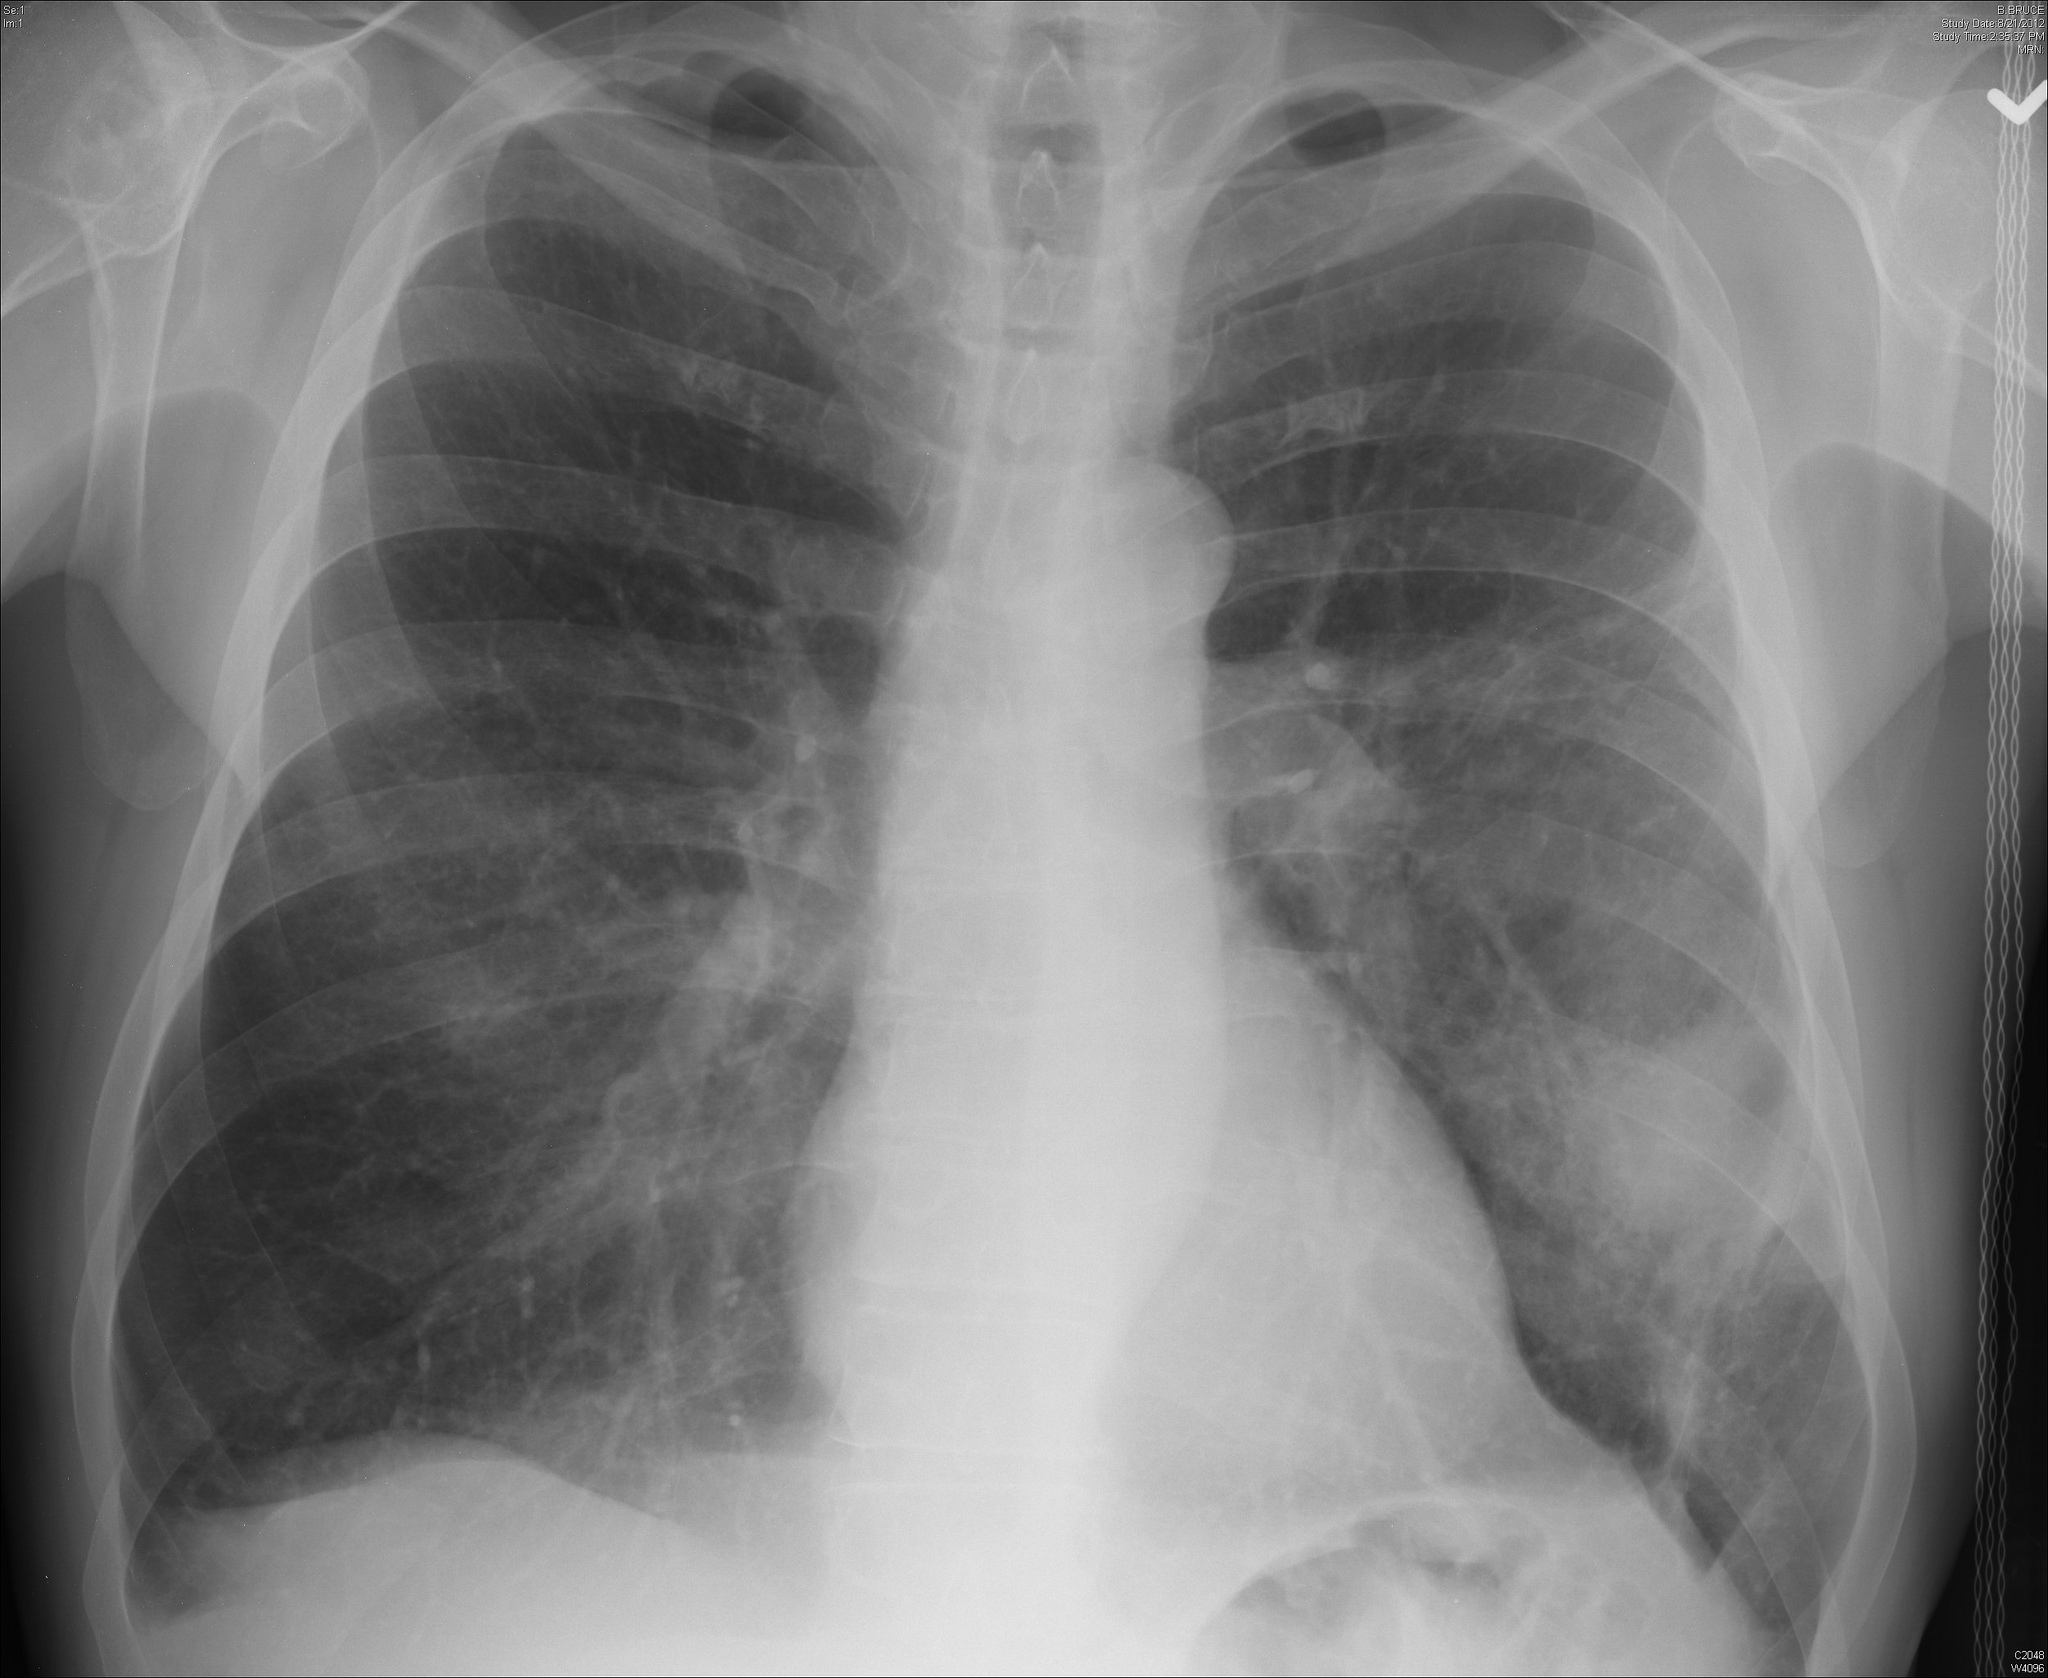

Pneumonia is an infection that inflames the air sacs (alveoli) in one or both lungs. The alveoli may fill with fluid or pus, causing cough with mucus or pus, fever, chills, and difficulty breathing. Pneumonia can range in seriousness from mild to life-threatening. People with chronic illnesses or weakened immune systems at a higher risk for serious complications.